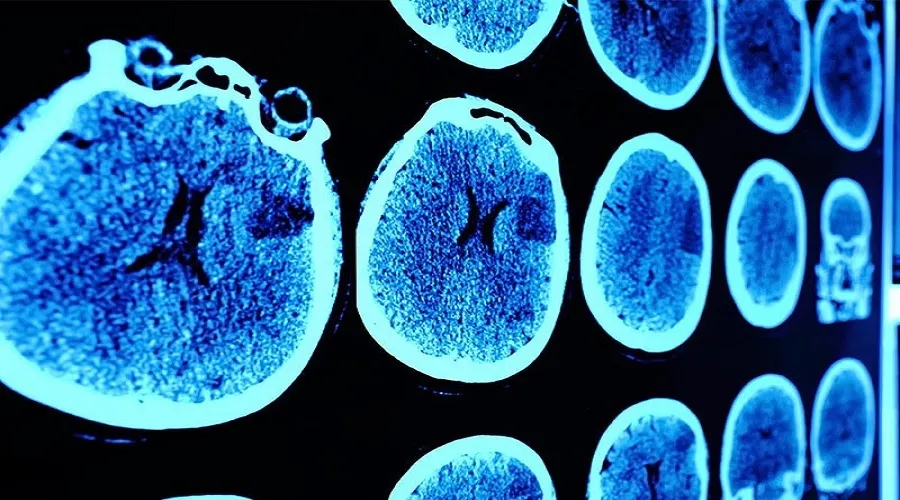

گلیوبلاستوما بهعنوان شایعترین و مرگبارترین سرطان مغز در دنیا شناخته میشود و تاکنون در برابر انواع درمان های مختلف مقاومت کرده است. معمولا وقتی پزشکان متوجه میشوند که کسی به این سرطان وحشتناک مبتلا شده است، به بیمار میگویند بین ۱۲ تا ۱۵ ماه برای لذت بردن از این دنیا فرصت دارد.

گلیوبلاستوما در مغز و نخاع رشد میکند و توسط سازمان جهانی بهداشت بهعنوان یک تومور سطح ۴ شناخته میشود. به این معنی که خشنترین نوع سرطان است. هر ساله ۳۲۰۰ نفر در بریتانیا به این نوع سرطان مبتلا میشوند که نسبت به ۱۲۷۰۰ مورد سرطان مغز و سیستم عصبی بسیار قابل توجه است. بهطورکلی میتوان گفت که سالیانه ۳.۲ تا ۴.۲ نفر از میان هر ۱۰۰ هزار نفر به گلیوبلاستوما مبتلا میشوند. بهبیان سادهتر هر ساله ۱۵۰ هزار نفر اسیر این نوع سرطان مغز در جهان خواهند شد.